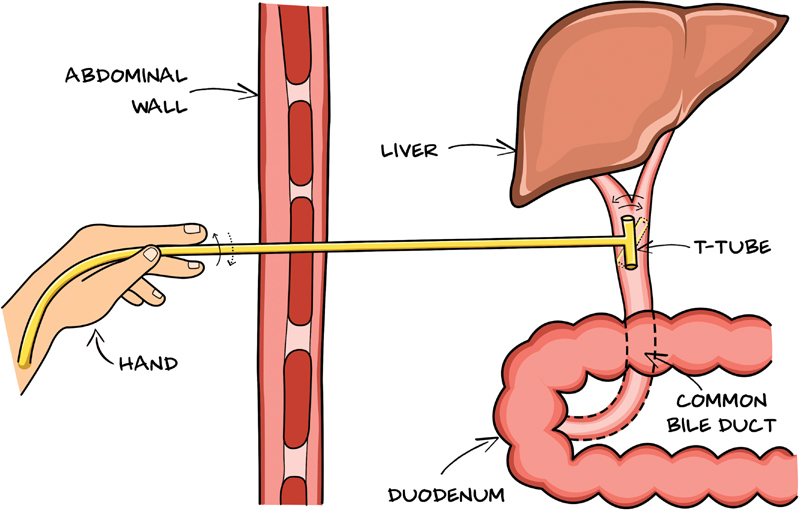

On follow-up at 3 weeks, the patient was doing well, and hence, T tube removal was planned. However, it got fractured at the junction between the short and long limbs on attempted removal, and only the long segment of the T tube could be retrieved. The patient was admitted and kept under close monitoring. A plain X-ray abdomen was done, which showed radiopaque linear intensity over the right paravertebral location suggestive of a retained T tube fragment. MRCP showed dilated CBD ∼9.3 mm with a T tube remnant approximately 2 cm length, in mid and distal CBDs ( Fig. 2 ). ERCP, done this time by a different endoscopist, showed a radiopaque structure in the mid and distal CBDs, retrieved by balloon catheter postsphincterotomy followed by the placement of a bile duct stent ( Fig. 3 ). T tube fragment was inspected for its entirety ( Fig. 4 ). No adverse events were reported at 2 weeks to follow, and the CBD stent was removed without any subsequent complications.

The T tube should be initially rolled between the thumb and the index fingertips and subsequently flushed with normal saline if it does not come out quickly ( Fig. 5 ). Any retained T tube fragment should be retrieved immediately to avoid early and late complications. As there is no standard method to retrieve retained T tube fragments, endoscopic removal, even though technically challenging, is safe and effective and should be attempted first to avoid major second surgery.